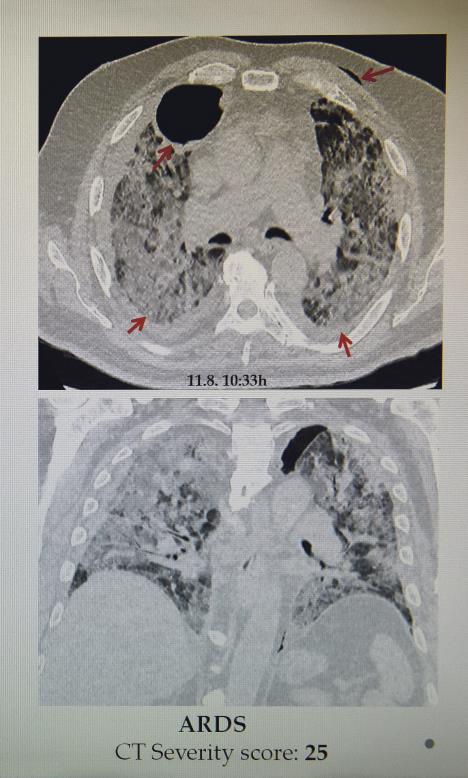

On dodaje da postoje četiri faze kroz koje prolaze pluća pacijenta s kovidom 19, a da na skeneru skor ide od 0 do 25, koji je i najgori i smrtonosan.

- Najpre ide takozvano mlečno staklo, kada se najmanji delovi pluća pune tečnošću, a što ne može da se vidi na rendgenu. Onda se pluća popločavaju, što vodi ka zapaljenju, i dolazimo do treće faze - konsolidacije, koja je i vrhunac bolesti, gde je pneumonija, najčešće obostrana, u punom jeku. To je neki 11-12. dan bolesti i nakon toga ili spasemo pacijenta ili, nažalost, sledi ARDS - akutni respiratorni distres sindrom, koji se završava fatalno - objašnjava dr Lalošević. On nam je pokazao snimak pluća pacijenta sa skorom 25, koji je preminuo na respiratoru, kao i pacijenta koji je takođe imao katastrofalan skor - 23, a uspeo je da se izvuče.